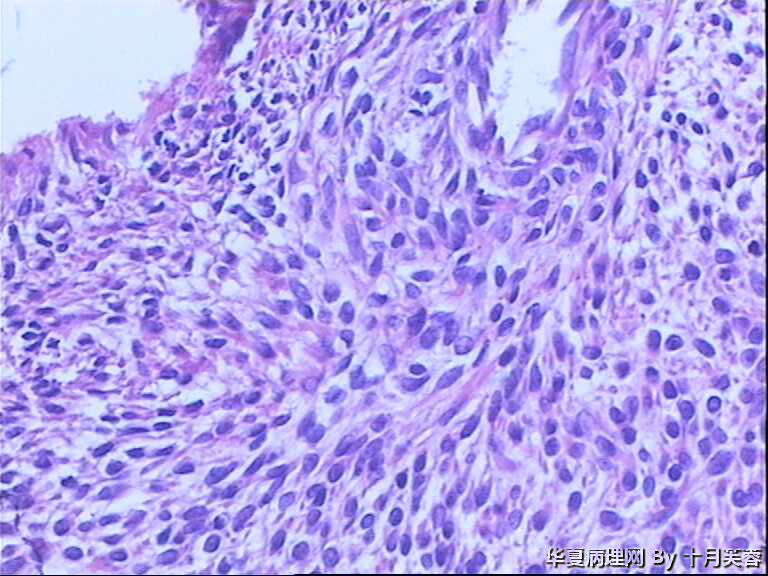

女性,50岁,临床申请单“子宫肌瘤穿刺”

• 子宫肌瘤穿刺图1

图1

平滑肌瘤?间质肿瘤?